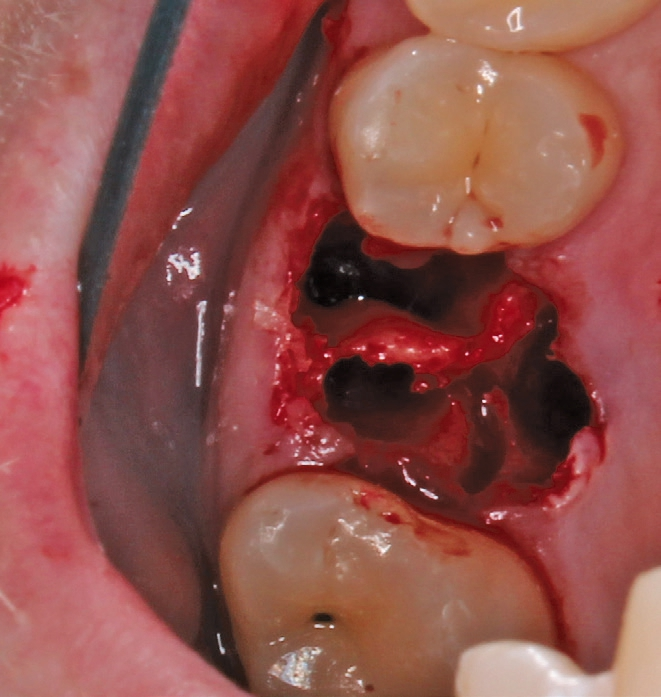

Ein 21-jähriger Patient stellte sich mit einer Perkussionsempfindlichkeit in regio 26 vor. Die klinische Untersuchung zeigte einen tiefzerstörten Zahn 26, dessen gesamte palatinale Wand tief fraktruiert war. Die Frakturgrenze verlief dabei weit unter dem palatinalen Zahnfleischrand (Abb. 1). Nach Erstellung eines Orthopantomogramms und einer radiologischen Einzelzahnbildaufnahme war eine längliche Verschattung am Apex der palatinalen Wurzel des Zahn 26 zu erkennen (Abb. 2), die den Verdacht einer überinstrumentierten Wurzelkanalaufbereitung der palatinalen Wurzel und einer Überstopfung des Füllmaterials bestätigte (Abb. 3). Nach konservierender Theapie wurde die Indikationsstellung für die Extraktion des Zahnes 26 mit einer Sofortimplantation gestellt. Der Periodontal-Screening-Index wies in allen Sextanten Grad 2 auf. Es folgte die Erstellung einer dreidimensionalen Röntgenaufnahme (Orthophos XG 3D, Dentsply Sirona, Bensheim) zur virtuellen Planung der Implantatposition. Die operative Planung erfolgte in der Planungssoftware coDiagnostiX 9.5 (dental wings, Montreal, Kanada) (Abb. 4).

Die Operation erfolgte in Lokalanästhesie (Ultracain® D/S forte, Aventis, Frankfurt) in Form einer Infiltrationsanästhesie bukkal und palatinal der Region 26. Mittels der Instrumentenspitze EXP4-L (Piezosurgery, Mectron, I-Genua) wurden die dentogingivalen Fasern vorsichtig durchtrennt und der Desmodontalspalt geweitet (Abb. 5 und 6). Nach Durchtrennung der Wurzeln wurde der Zahn mit einer Extraktionszange aus dem gelockerten Zahnfach vollständig entfernt (Abb. 7 und 8).